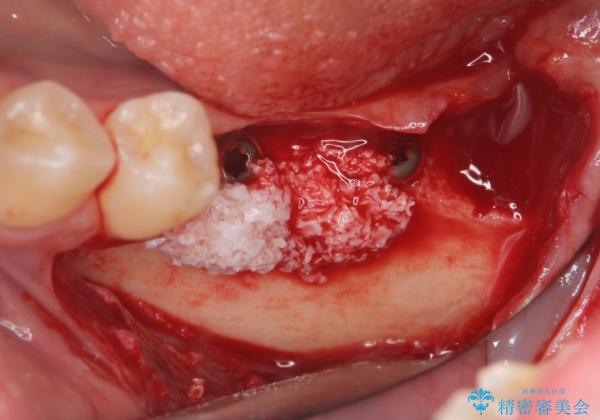

CT画像より骨の量は少なくそのままではインプラントの埋入が難しい状態です。

骨造成を行い安定したインプラントの環境を整える治療を計画します。

インプラントの長期的な予後を見込むには、インプラント周囲の安定した十分な骨量や清掃性、角化歯肉の存在が重要です。